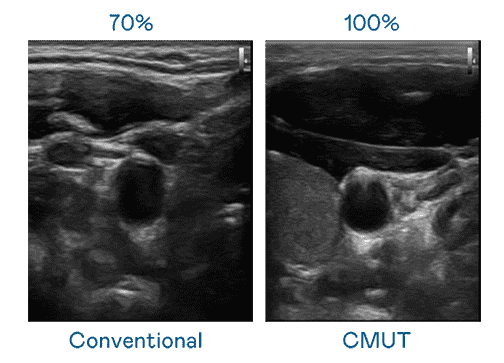

CMUT 技术是一种用电容式微机电元件来产生超音波讯号的技术。。。与传统 PZT 压电式技术相比,,,CMUT 频宽增加 30%,,,更宽频的超音波讯号让影像解析度大幅提升,,,,是实现高影像品质医疗超音波扫描、、、促进精准医疗发展的关键技术。。。

大频宽带来超清晰影像

超音波影像的解析度高低,,,首先取决于探头能发出的讯号频宽。。PG国际 CMUT 可提供高清晰的超音波讯号,,,,提供高频宽、、高灵敏度、、、、影像纹理细节更高的超音波影像,,协助医护人员缩短影像判读时间及利用精准的医疗影像进行诊断。。